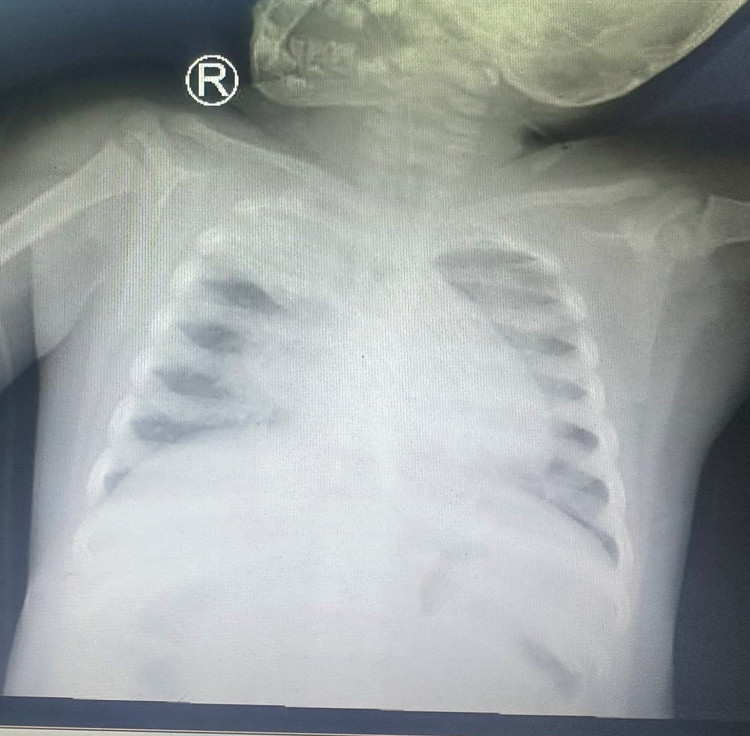

| Xquang phổi: tổn thương lan tỏa 2 bên phổi, xẹp đỉnh phổi (P) - Ảnh: BVCC |

Tình trạng lúc nhập viện, trẻ li bì tím tái, SpO2 80-82% với thông số máy thở cao (chế độ kiểm soát áp lực tần số 30 lần/phút, IP 24 cmH2O, PEEP 14 cmH2O, FiO2 80%, khí máu động mạch cho thấy tình trạng thiếu oxy máu nặng, chỉ số oxy hóa máu OI: 32, biểu hiện hội chứng suy hô hấp cấp tiến triển nặng (ARDS acute respiratory distress syndrome), Xquang phổi: tổn thương lan tỏa 2 bên phổi, xẹp đỉnh phổi (P). Chẩn đoán: Viêm phổi nặng – ARDS nặng do cúm A/H1 pdm 2009.